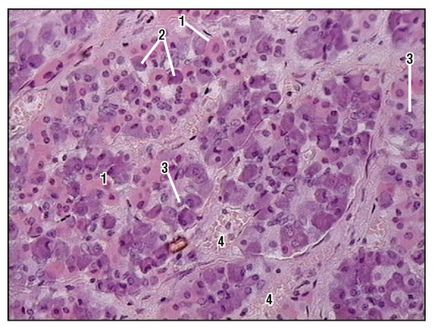

Fig. 165. Parte periferică a pituitară (fragment) (colorată cu healon, creștere medie):

1 - celulă acidofilă; 2 - celulă bazofilă; 3 - o celulă cromofobă; 4 - capilare sinusoidale